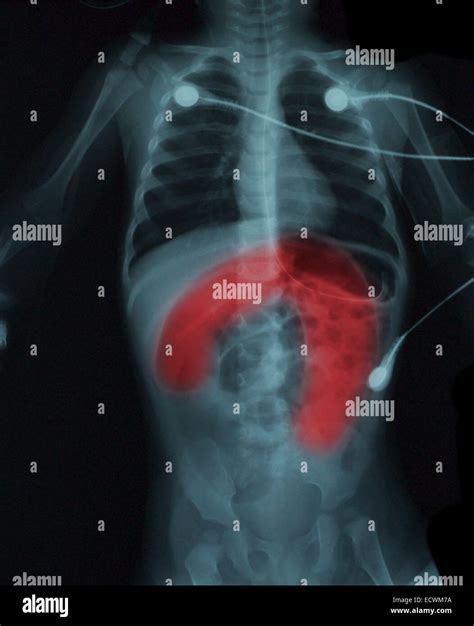

Foreign Bodies X-rays can locate foreign bodies, such as swallowed objects or inhaled items, which may require removal.

• Radiologist Review: The X-ray images are reviewed by a radiologist, who will look for any signs of fractures, infections, or other abnormalities.

• Report Generation: A detailed report is generated, outlining the findings and recommendations for further action.